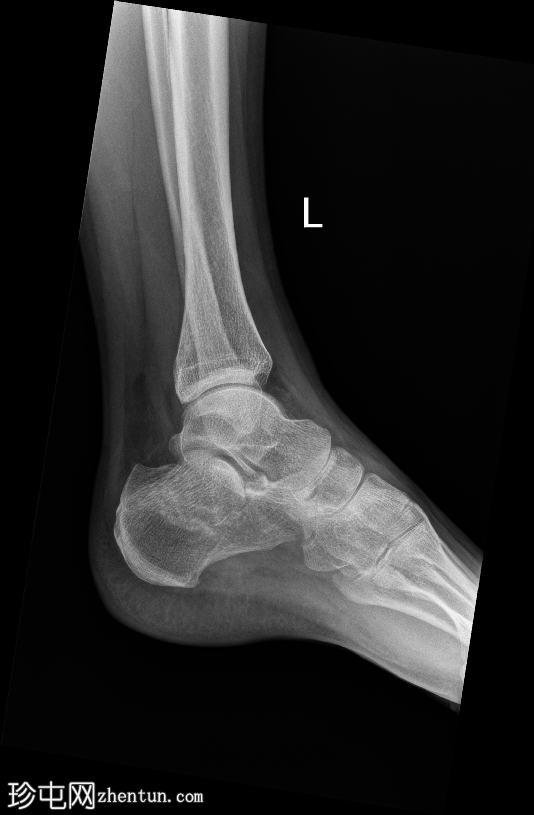

斜位片

左侧跟骨关节内粉碎性骨折。骨折线贯穿跟骨体,累及并破坏距下关节后关节面,并沿跟骨外侧可见一处骨折。骨折始于距下关节中央,向下向后延伸。跟骨整体高度降低,后关节面凹陷,Böhler角变平,Böhler角明显减小,提示后关节面凹陷。

距骨、舟骨以及外踝和后踝均完整,踝穴和韧带联合完整。距下关节和跟骰关节未见脱位。软组织肿胀亦可见。

跟骨骨折是跗骨中最常见的损伤,通常由轴向负荷力引起,例如高处坠落或高强度冲击创伤。本例左侧跟骨的侧位片和轴向片显示,关节内粉碎性骨折延伸至距下关节后关节面,伴有高度降低和后关节面凹陷。

Böhler角(由跟骨前后关节面连线的交点定义)显著减小(约5-10°,正常值为20-40°)。Böhler角的减小反映了后关节面的塌陷,并提示跟骨结构性损伤严重。

Sanders 分类根据跟骨后关节面的 CT 表现对关节内骨折进行分类,根据该分类,该损伤很可能属于 II 型或 III 型骨折。这些类型涉及一条或多条穿过后关节面的骨折线,并伴有不同程度的粉碎和移位。